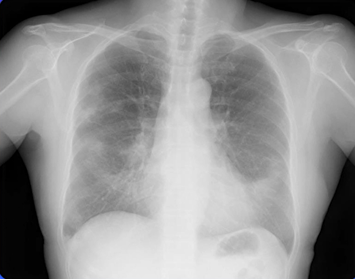

中葉舌区症候群(SBS: Middle Lobe and Lingula Syndrome)のレントゲン(X-p)

中葉舌区症候群(SBS: Middle Lobe and Lingula Syndrome)とは、右肺の中葉と左肺の舌区に、無気肺(肺の一部が虚脱した状態)や慢性的な炎症が起きたことによって生じる一連の症状です。主症状は「頑固で多量の痰」と「血痰」で、その他に慢性的な咳嗽、発熱、胸痛などがみられることがあります。

本症例のレントゲンでは、右中肺野の浸潤影が明らかです。

右2弓、左4弓(心臓と接した舌区)とシルエットサイン陽性の浸潤影も認めます。

以上から、中葉・舌区病変→中葉舌区症候群(SBS)を最も疑いますが、NTM感染も否定はできません。精査に進みます。